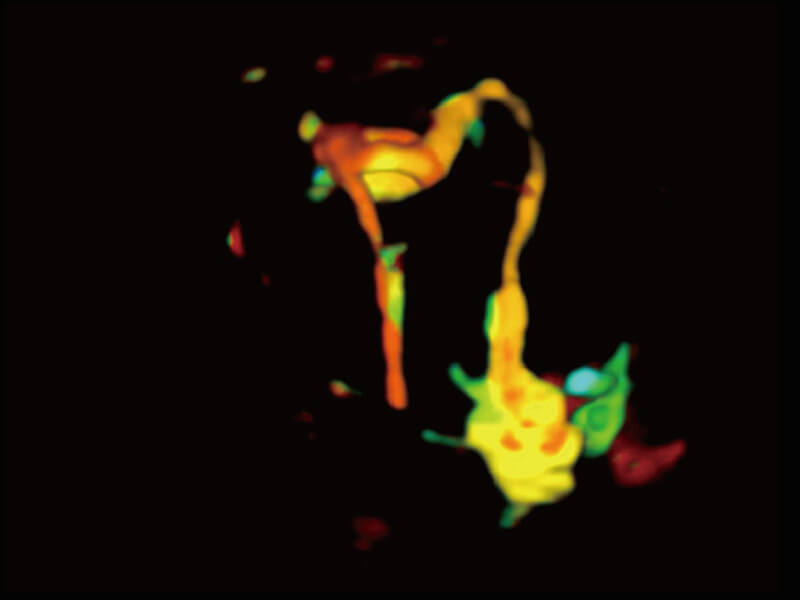

成像功能

S60探头工艺,从前端信号处理每一个环节采集无损声学数据,真实还原组织原貌,再现解剖细节。